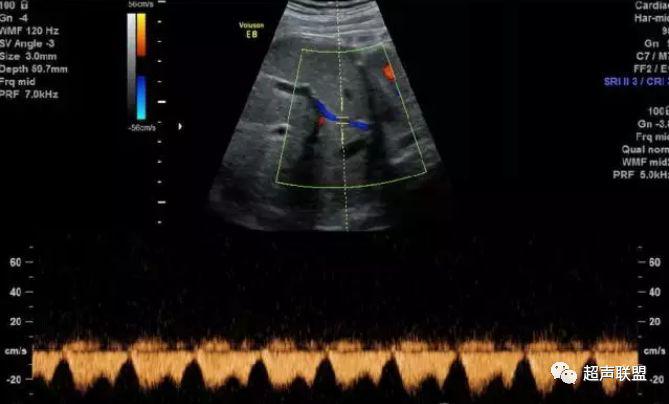

5 子宫动脉血流测定

正常妊娠时血流速度增加,血流阻力下降。缺氧早期的血流再分配,子宫动脉血流RI、PI值增加,阻力指数(RI)>0.57,子宫动脉血流频谱出现切迹。

3、子宫动脉标准:孕26或27周后,子宫动脉S/D>2.7,(RI)>0.57,有舒张早期切迹;

图7 正常中孕期子宫动脉频谱

图8 胎儿宫内缺氧,子宫动脉舒张早期可见切迹